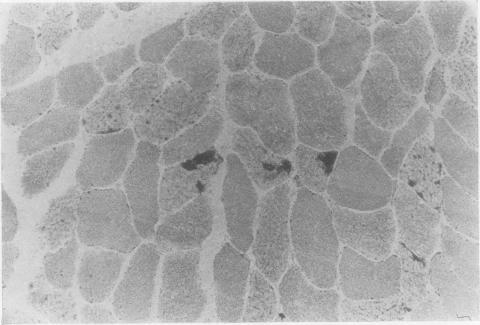

Skeletal muscle samples, mainly from the deltoid, were studied morphologically and histochemically in 35 patients with chronic heart block and from nine elderly control subject. The average age of the first group was 67-7 (range 11-94) years. Abnormalities were present in 20 cases, no difference being found between patients with idiopathic and secondary heart block. In 15 samples there was increased oxidative enzyme activity in some muscle fibres, and in six there was fibre type grouping. Six had unexplained type 11 fibre atrophy and two had a predominance of type 1 fibres. Tubular aggregates were conspicuous in one biopsy specimen, and in another, rod bodies were found. Minor abnormalities were also seen in the control group. In the absence of any consistent pattern many of these changes were attributed to ageing.